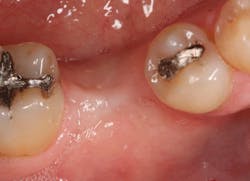

Stage II uncovering was performed five months following the initial surgery. A crestal incision was made toward the lingual ridge to split the keratinized gingiva, as that is where the keratinized gingiva had settled following surgery due to the coronal advancement of the buccal flap to obtain primary closure. The keratinized gingiva was buccally positioned, and a healing abutment was placed. The tissue was sutured with 4.0 chromic gut. This allowed the attached gingiva to heal on the buccal portion of the healing abutment and thus remain on the buccal portion of the final restoration. Final impressions were taken two weeks later, and the restoration was delivered thereafter.

The patient returned three and six months later for a postdelivery radiograph and healing check. The peri-implant tissues were healthy with no abnormal bleeding or probings. The patient reported high satisfaction with his new implant restoration.